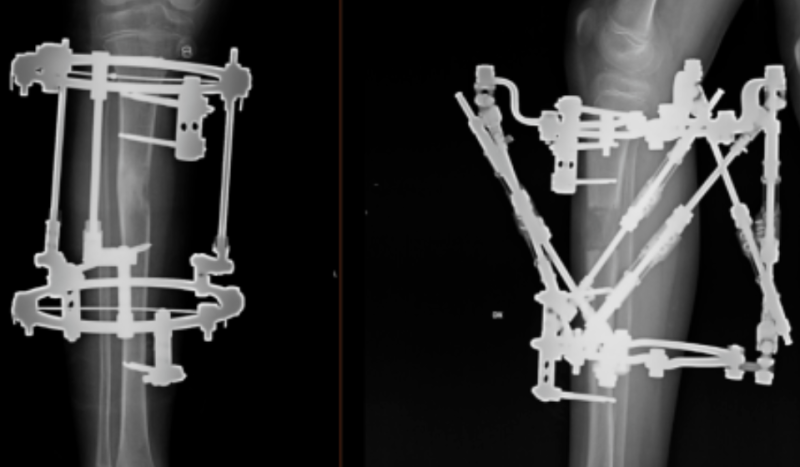

1. Ekstremitāšu rekosntruktīvā ortopēdija nozīmē operāciju un tai sekojošu operētās zonas korekciju ar ārējās fiksācijas aparāta, t.s. ortopēdiskā heksapoda palīdzību.  Operācija noris, izmantojot spinālo vai vispārējo anestēziju, un ilgst līdz 2 stundām. Pacientam klīnikā jāuzturas vienu diennakti.

2. Operācijas laikā tiek veikta osteotomija (kontrolēts lūzums) un uzstādīts ortopēdiskais heksapods – ārējās fiksācijas aparāts, ar kura palīdzību iespējams veikt gandrīz jebkuras deformācijas precīzu korekciju.

5. Pēc deformācijas korekcijas pacientam tiek noņemta lielā ortopēdiskā heksapoda konstrukcija - ap koriģējamo ekstremitāti paliek tikai 2-3 fiksācijas gredzeni, kuri neierobežo pacienta mobilitāti.

Ekstremitāšu rekonstruktīvā ortopēdija notiek ķirurģiski ar ārējās fiksācijas - t.s. ortopēdiskā heksapoda palīdzību.